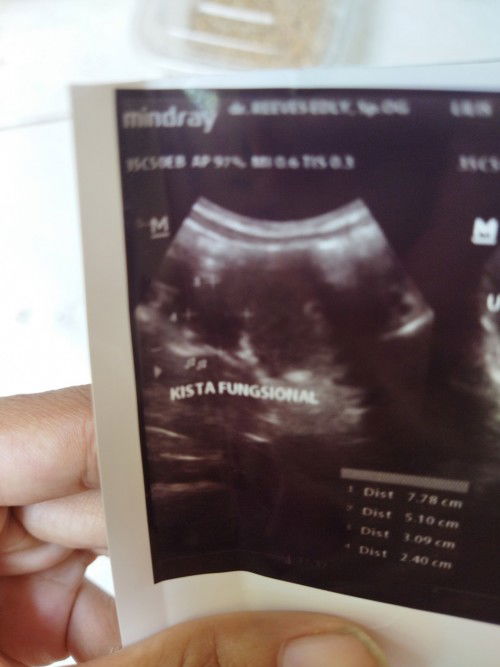

coba ganti dokter bun, setau sy kalo sudah + itu memang terdeteksi hormon kehamilannya, tp mungkin masi terlalu dini untuk bisa terlihat di layar USG. dulu saya 9w baru keliatan kantong

usia brp w bun? biasanya dibawha 5 w baru penebalan hamil. saya alhamdulillah gak ada kista, usia 6w baru ada kantong

waktu USG 5 W 4 hari bun